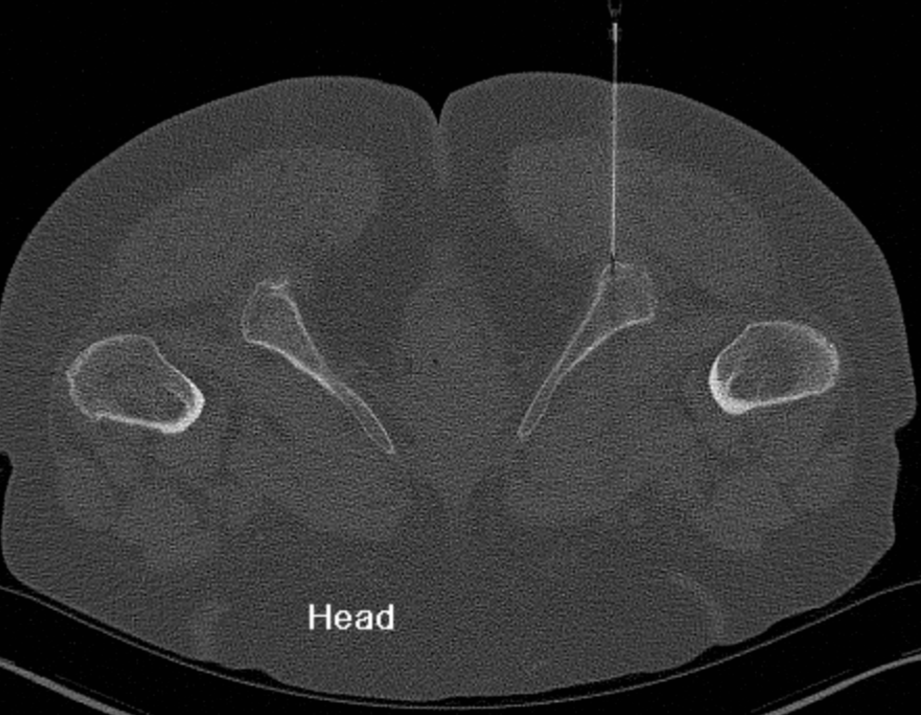

3. Common Hamstring Tendon Origin injection